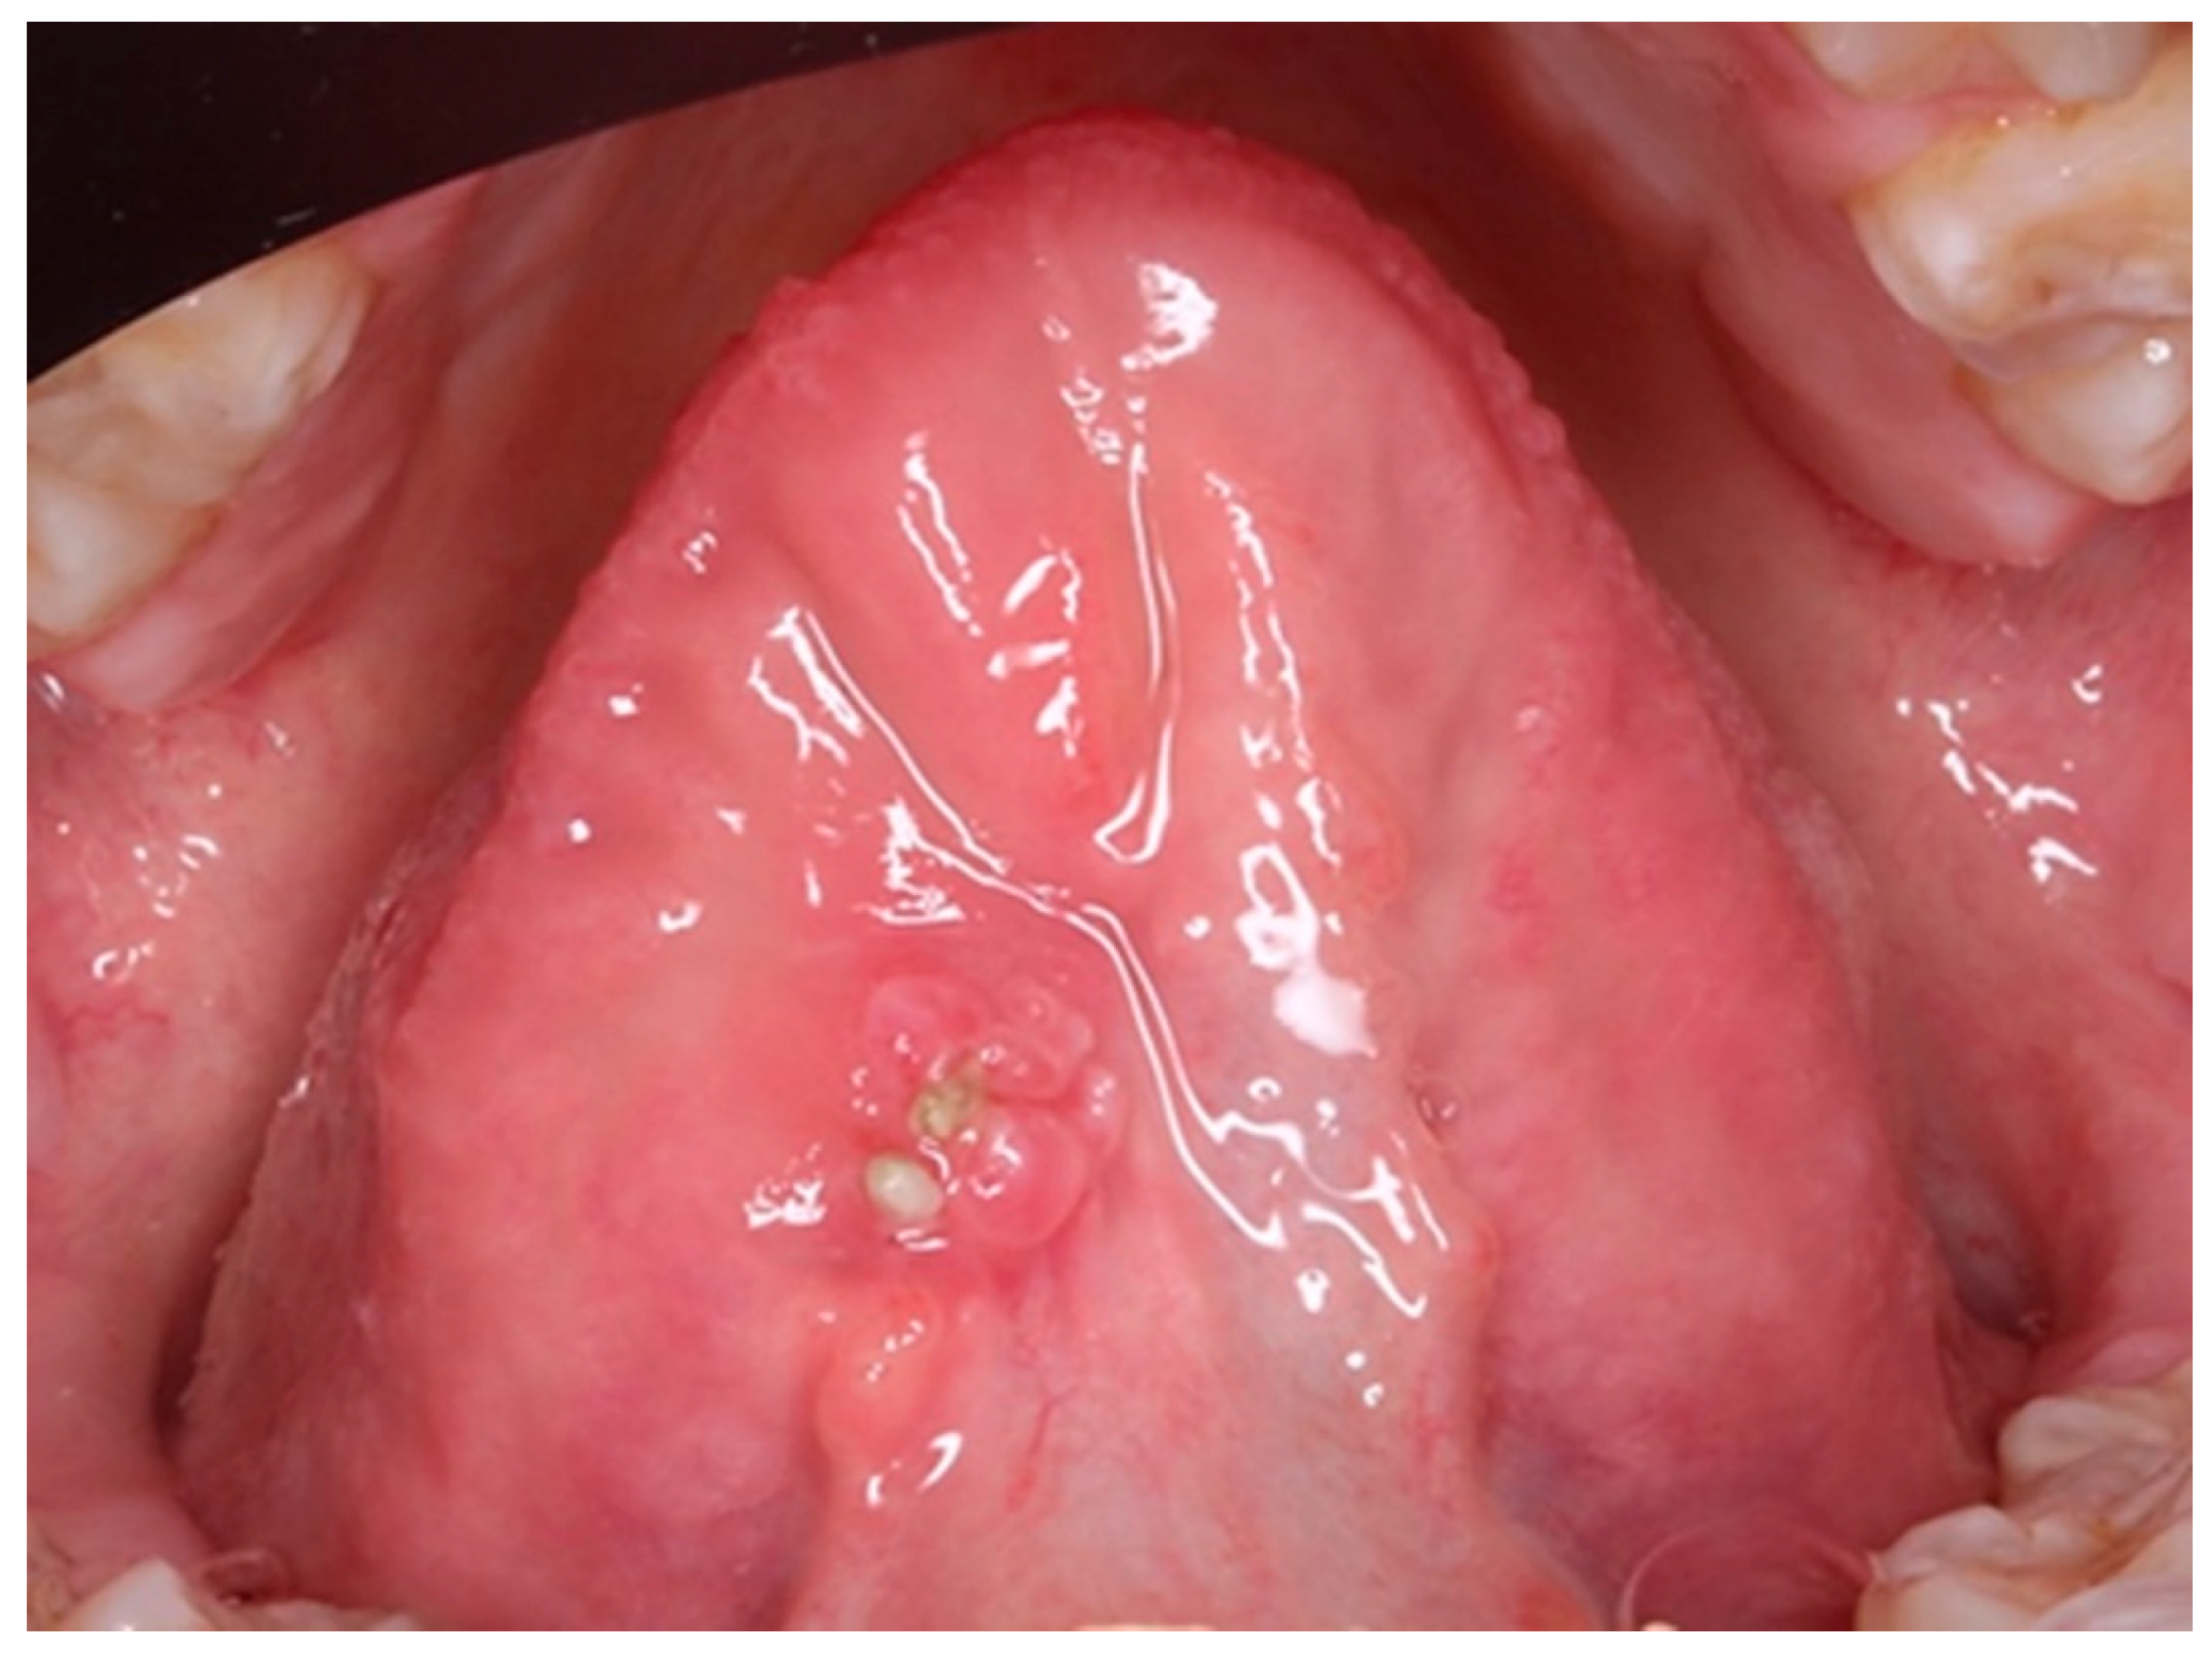

Undoubtedly, the time of evolution of the lesion makes it essential to carry out a biopsy in order to classify the pathology and establish the correct treatment. On the other hand, when we are faced with a large lesion (see Fig. 1), the question arises as to whether we should perform an excisional biopsy or take a representative sample and wait for a histopathological diagnosis.

Figure 1.

Preprints 77661 g001

After histopathological study, the lesion was diagnosed as Traumatic Eosinophilic Granuloma of the Oral Mucosa (TUGSE). This is a rare pathology characterised by the appearance of a single ulcerated lesion that may be asymptomatic and predominantly located on the tongue.18 The appearance of the lesion may be confused with a squamous cell carcinoma, which causes concern for the patient and family members. The lesions are self-limiting, but may take months or up to a year to disappear, which complicates diagnosis and decision-making. This type of lesion was described as its own entity by Saphiro and Juhlin19 in 1970, and when it occurs in infants, it is comparable to the pathology catalogued as Riga-Fede disease and characterised by the presence of traumatic ulcers resulting from the appearance of connatal or early erupting teeth. It usually appears from the 5th decade onwards, which leads to a greater suspicion of carcinoma than when it is a lesion in children 20. In the different studies, no consensus has been found on the existence of a gender predilection21,22,23.

Clinically, the lesion usually has a raised hyperkeratotic border and microscopically it is characterised by a dense infiltrate of T and B lymphocytes, macrophages and mainly eosinophils24 and a tendency to penetrate the underlying muscle.

a) Macroscopic description: 1.3x2 cm round fragment with 1.2 cm ulcer with raised edges and granular central area. Two samples are submitted, one from the central area and one from the periphery.